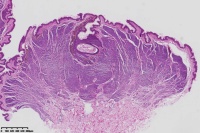

背部包块,皮内痣?

性别

女

年龄

41岁

背部包块

图1

考虑符合:皮内痣

皮内痣

皮肤皮内痣,切缘未净